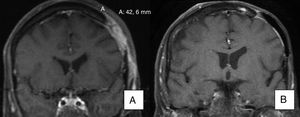

El tratamiento fue administrado durante 11,8 meses de media. En 9 de nuestros pacientes (41% de los casos) se obtuvo una respuesta completa al tratamiento (fig. 1A y B); 10 de nuestros pacientes (45% de los casos) obtuvieron una respuesta parcial (fig. 2A y B, figs. 3 y 4A-D) y en 3 de los pacientes (14% de los casos) vismodegib consiguió estabilizar la enfermedad.

Varón de 50 años con CBC infiltrante de 8×8cm localizado en cuero cabelludo con exposición ósea (A). Recibió vismodegib con inicio de respuesta el primer mes y con respuesta máxima a los 8 meses (B). Actualmente, libre de enfermedad desde hace 13 meses (caso 13 en la tabla 1).

Varón de 73 años con CBC esclerodermiforme de 3×3cm localizado en canto interno (A). Obtiene una respuesta parcial tras 6 meses de tratamiento (B) (caso 6 en la tabla 1).